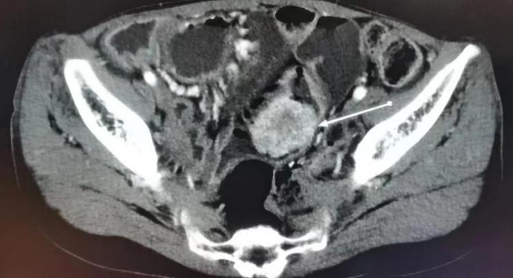

根据周女士情况,医生分析,CT影像显示小肠末端有巨大占位,息肉直径约8*5cm,由于多次手术已经造成肠粘连,同时伴随肠套叠症状,常规切除方法都不能安全有效地解决问题。

患者检查影像。中山医院内镜中心主任周平红教授带领团队讨论周女士的治疗方案,虽然手术难度极高,目前国内外相关手术经验较少,但在多年积累的丰富经验和内镜下切除先进技术的支持下,内镜团队在做足了充分准备的前提下,决定再闯禁区,为周女士行小肠镜下巨大息肉切除术。